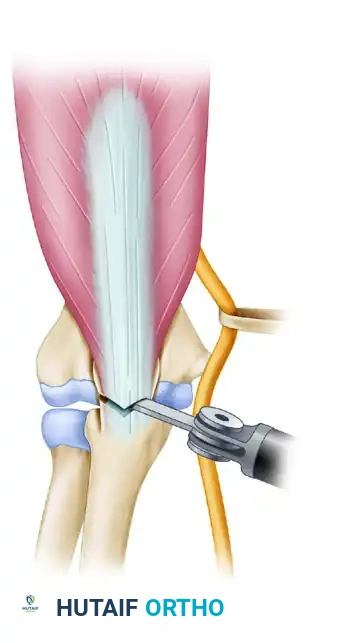

Osteotomized proximal olecranon elevated

The osteotomized proximal olecranon fragment is elevated proximally. The ulnar nerve is isolated, mobilized, and protected throughout this maneuver.

Raise the triceps with the proximal olecranon fragment, and dissect the triceps musculature off the posterior humerus, preserving the periosteum where possible.